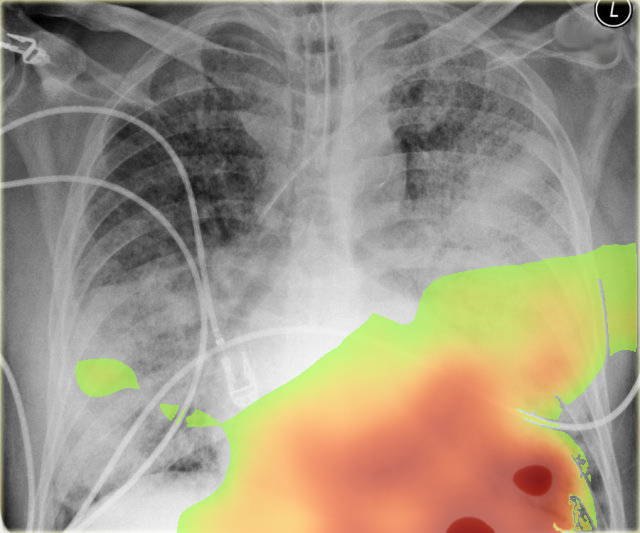

- Diffuse, bilateral airspace opacities involving both image-right (patient-left) and image-left (patient-right) lungs, confluent in the lower zones, consistent with alveolar filling.

- Relative sparing of apices but diffuse ground-glass and consolidation throughout mid-to-lower zones.

- No large pleural effusion or pneumothorax detected; costophrenic angles partially obscured by consolidation.

- Cardiothoracic ratio appears at the upper limit of normal but difficult to fully assess due to diffuse opacities.

The most likely diagnosis is acute respiratory distress syndrome (ARDS) or severe pulmonary edema. The diffuse bilateral alveolar infiltrates without clear focal consolidation pattern, presence of endotracheal intubation, and indistinct vascular margins raise suspicion. Cardiomegaly is not prominent, which argues slightly against isolated cardiogenic pulmonary edema, making ARDS from sepsis, aspiration, or severe infection more likely.